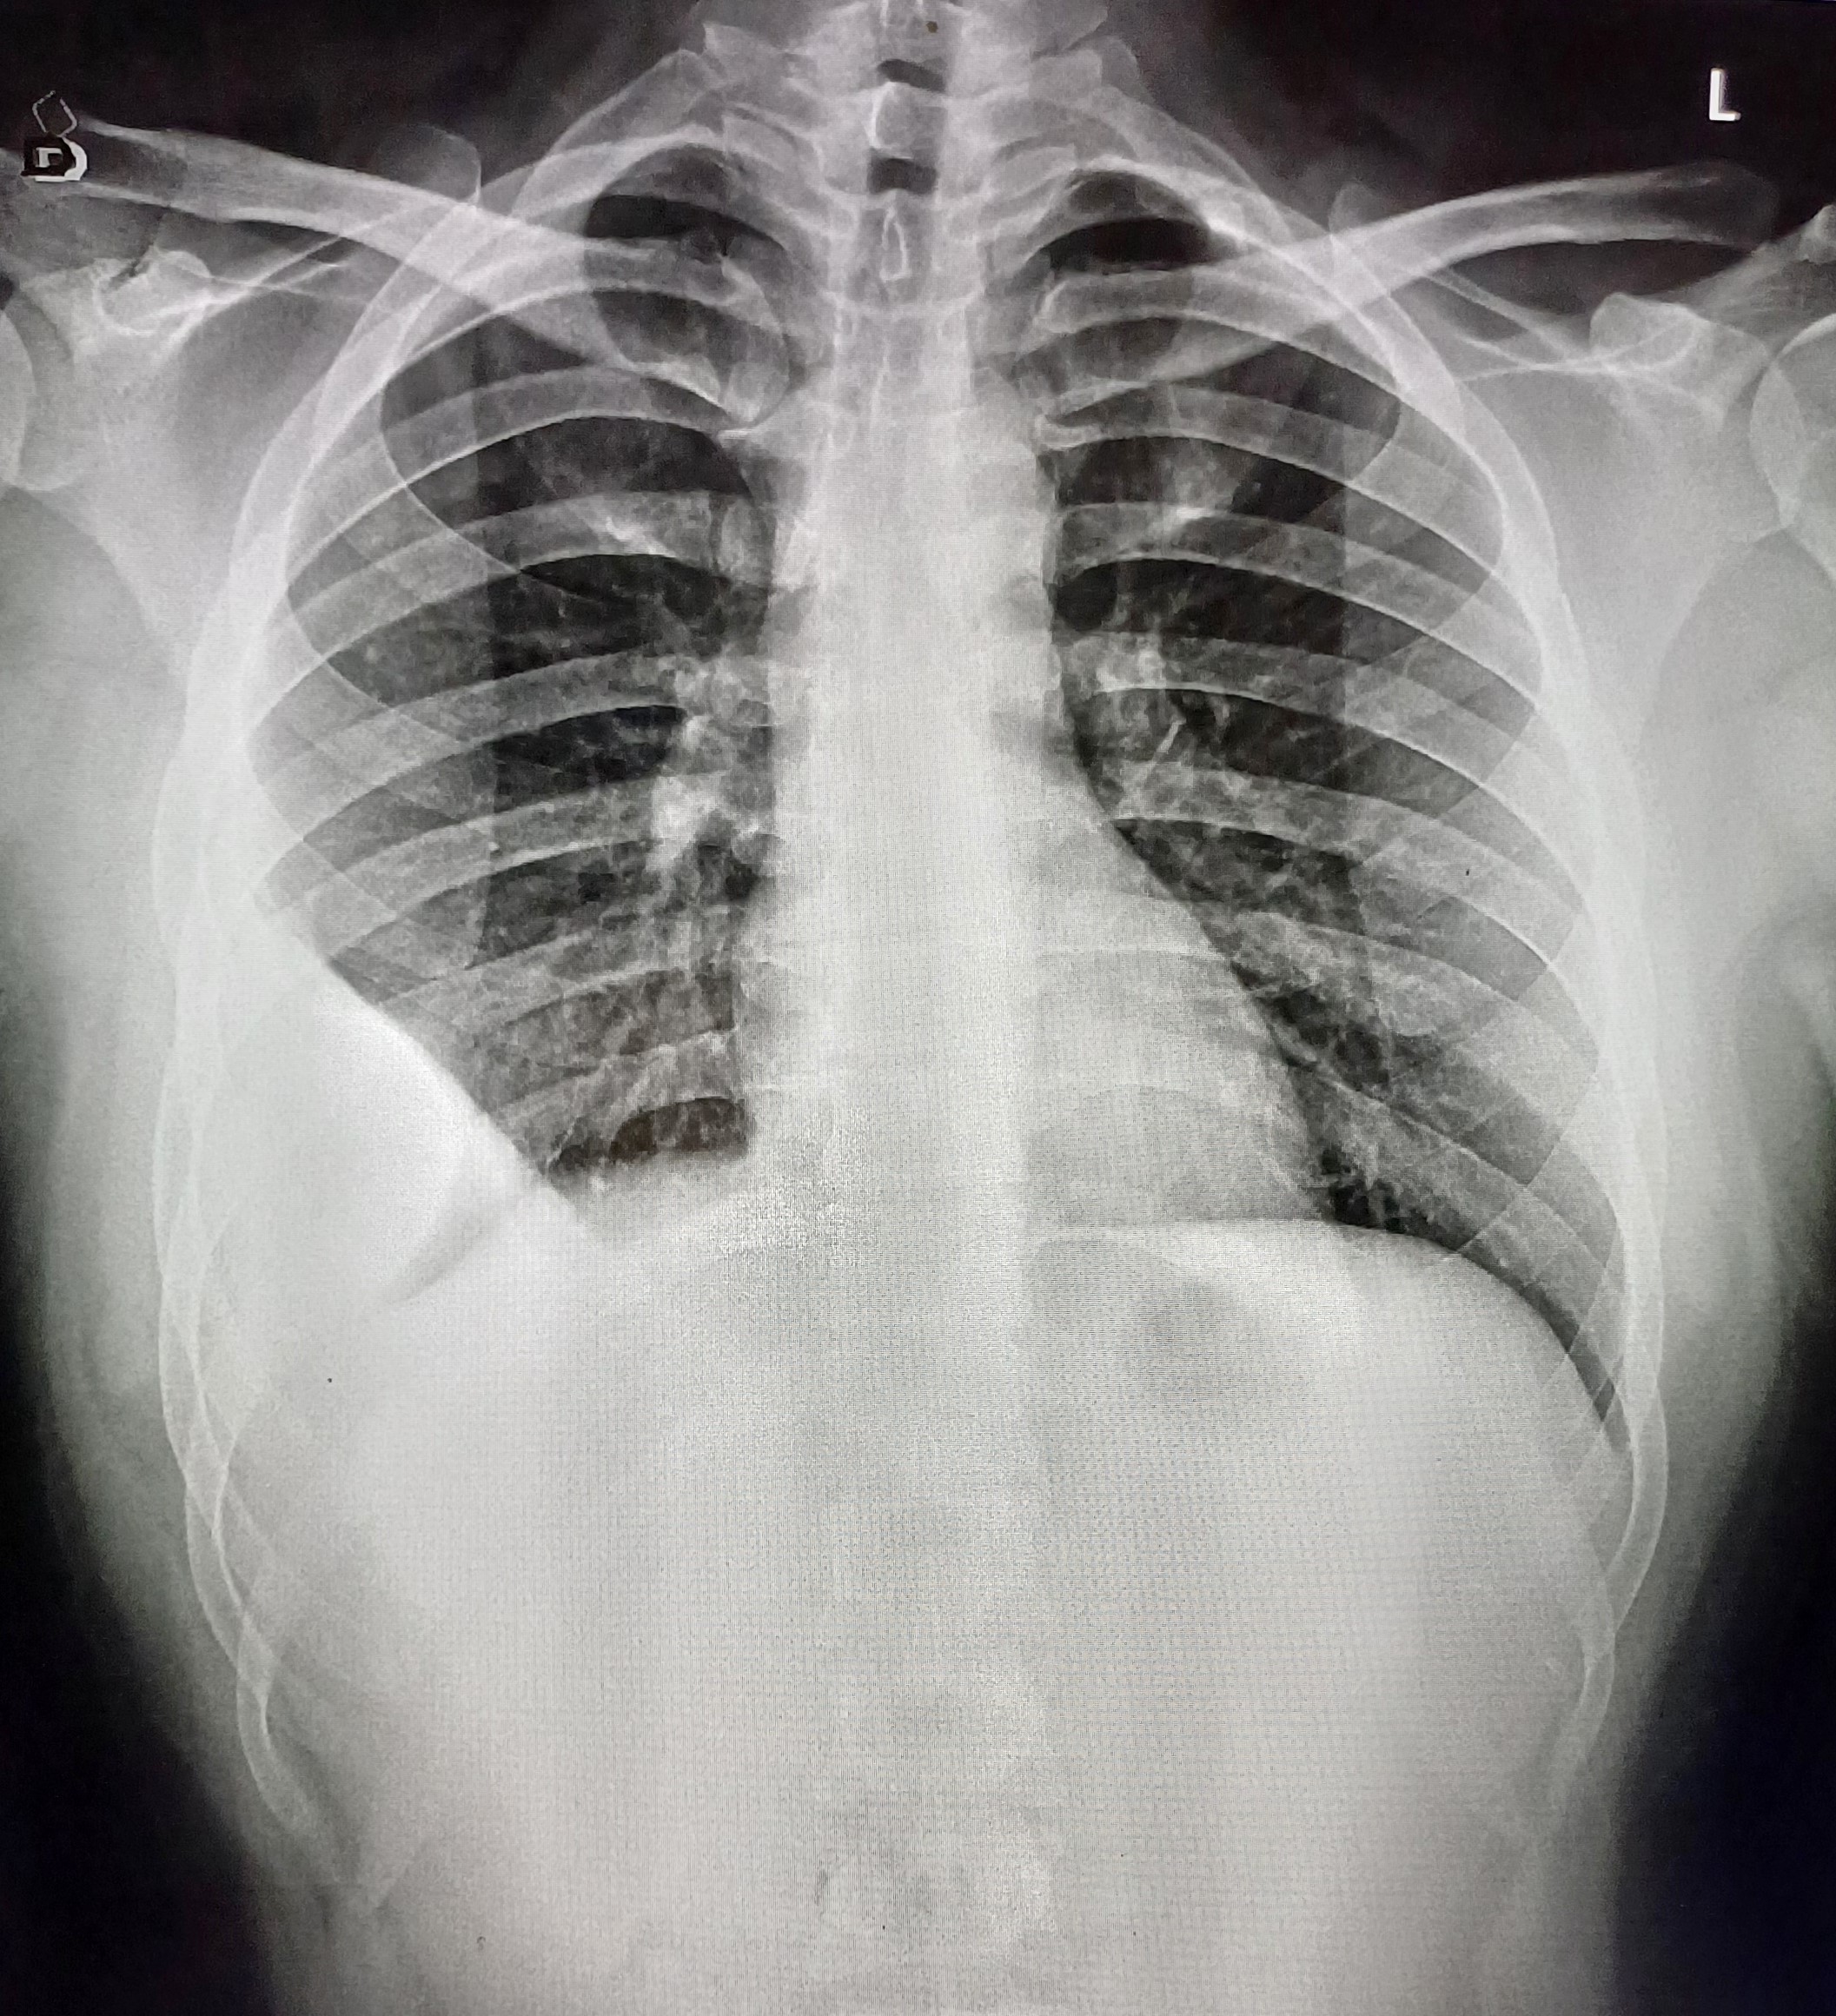

| 8 | IGGMC, Nagpur, Nagpur | P2 | 29-4464 | Shalu Chachane | Consent taken on Paper | 50 Yrs. |

Provisional Diag : Post TB Sequelae

Final Diag : Post TB sequalae (CxR- Bilateral Upper Zone Fibrocystic Changes) |

Post TB Sequelae | Bilateral Upper Zone Fibrocystic Changes | Abnormality visible on x-ray |